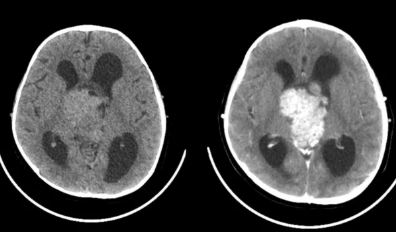

- 뇌/척수: 두통, 시야 흐림, 마비, 경련

초기에는 혈액검사, 엑스레이, CT, 림프절 조직검사, PET-CT 등을 통해 진단하며, 정확한 아형 분류 후 치료 방침이 결정됩니다.